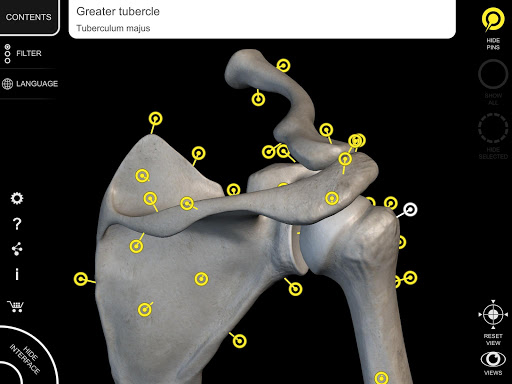

Mỗi xương của bộ xương người đã được tái tạo ở dạng 3D, bạn có thể xoay và phóng to từng mô hình và quan sát chi tiết từ mọi góc độ.

Bằng cách chọn mô hình hoặc ghim, bạn sẽ được hiển thị các thuật ngữ liên quan đến bất kỳ bộ phận giải phẫu cụ thể nào, bạn có thể chọn từ 12 ngôn ngữ và hiển thị các thuật ngữ bằng hai ngôn ngữ cùng lúc.

HÌNH GIẢI PHẪU 3D CÓ ĐỘ CHI TIẾT CAO

• Hệ thống xương

• Mô hình 3D chính xác

• Bề mặt của bộ xương có kết cấu độ phân giải cao lên đến 4K

• Ghim tương tác cho phép trực quan hóa thuật ngữ liên quan đến mọi chi tiết giải phẫu